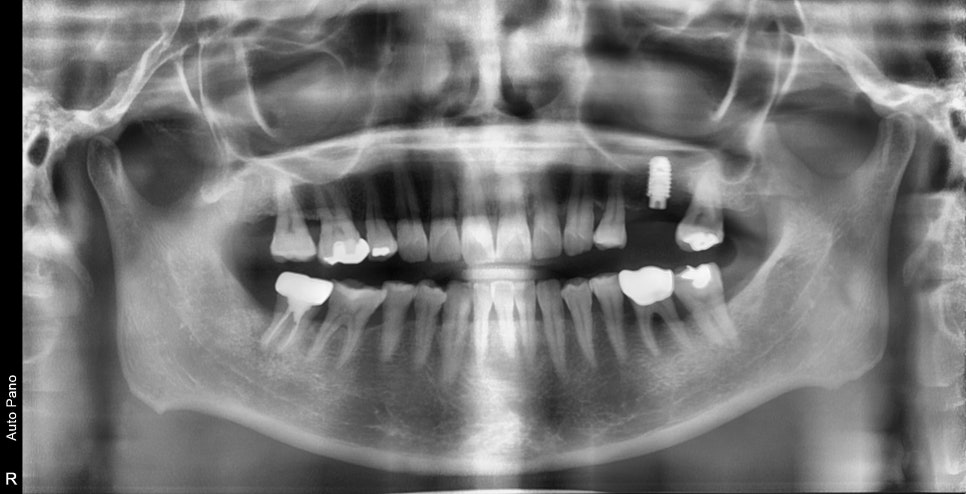

예를 들어

이렇게 사진상 진단시는 발치와 동시에 임플란트 수술이

가능했지만 제때 치료 시기를 놓치게 되면

시간이 지나 주변 뼈들이 염증에 의해 더 녹아

발치 후 치조골이식을 진행한 후

회복후 수술이 필요한 경우도 있습니다

노란 원으로 표시된곳이 치조골이식후 회복된상태입니다

물론 결과적으로 치료가 잘 마무리가 되지만

치료시기를 놓치게 되면 치료기간이 2배로 늘어날수 있습니다.

약 4개월후 빨간선으로 표시된것 처럼 주변 뼈들이 회복이 된것을 확인 후 임플란트 수술이 진행되었습니다.